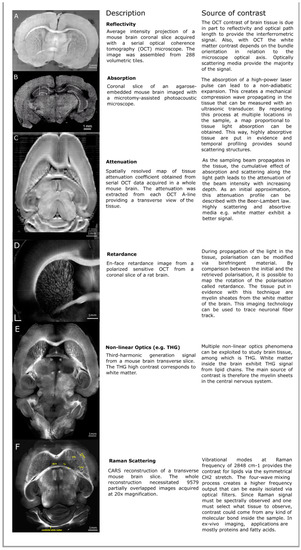

In this section, we review the distinct intrinsic optical contrast sources that can be exploited to image the brain. Representative brain images for each optical modality discussed in this section are illustrated in Figure 1. The light–tissue interactions presented are reflectivity and scattering, absorption, birefringence, nonlinear optical processes such as second- and third-harmonic generation, and Raman scattering. For comparison purposes, more details about the different imaging techniques are provided in Table 1.